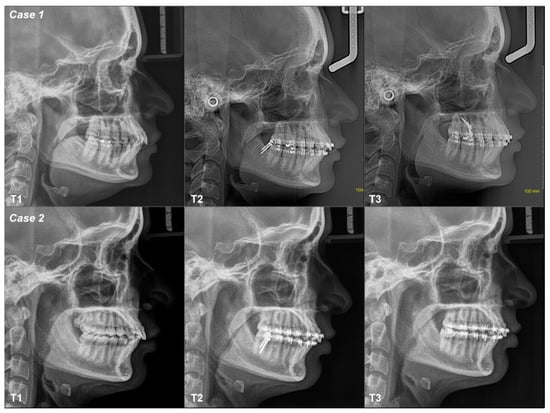

3.2.1. Case 1

3.2.2. Case 2